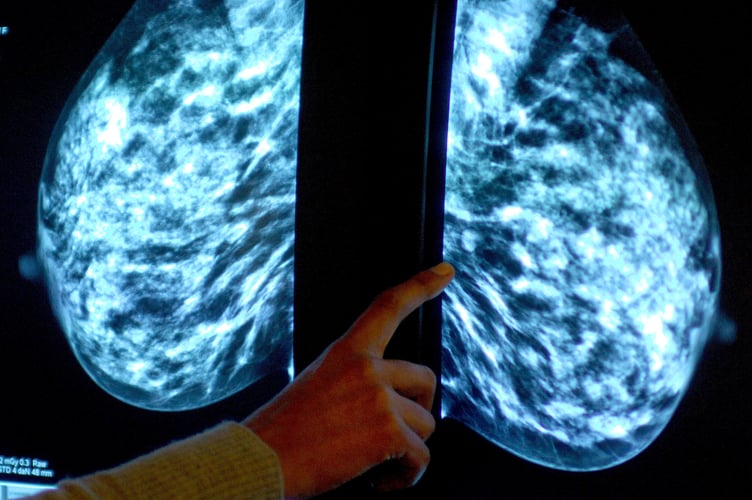

Breast screening uptake in Hampshire, Southampton and the Isle of Wight increased last year, new figures show.

Anyone registered with a GP as female will be invited for NHS breast screening every three years between the ages of 50 and 71.